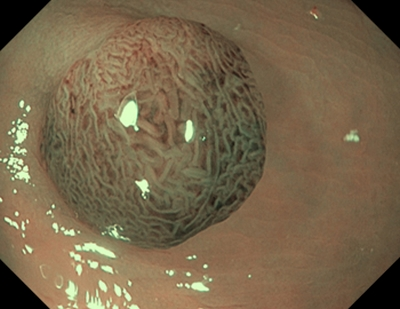

Тип 3 — характерний для злоякісної пухлини (ЗМ)

Колір: темніший за навколишнє, коричневий, іноді зі світлішими плямами

Судини: ділянки з перерваними або відсутніми судинами

Поверхня: аморфна або без малюнка на поверхні